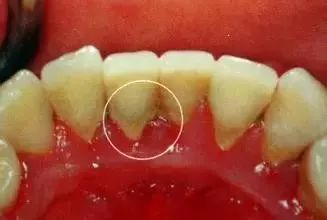

最严重的牙周炎通常被称为“进展性牙周炎”或“侵袭性牙周炎”,其特征包括:

牙龈严重萎缩和退缩:牙龈组织大量减少,牙齿根部暴露,牙龈边缘出现明显的凹陷。

牙龈溢脓:牙龈边缘可能有脓液渗出,表明存在明显的感染。

口臭和牙龈出血:这是牙周炎的常见症状,严重时可能伴随持续性口臭和牙龈出血。